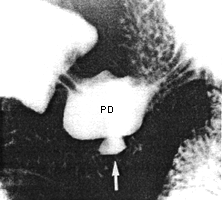

Case 22.2. G.V., 32 year old female, complained of a vague feeling of fullness and

occasional pain in the epigastrium. Physical examination revealed some epigastric

tenderness. After a month's treatment with antacids the symptoms disappeared.

Radiographic examination at that time showed a small diverticular-like structure on the

greater curvature of the pyloric sphincteric cylinder approximately 3.0 cm proximal to the

pyloric ring, i.e. midway between the right and left pyloric loops, in the position where

the pyloric pseudo-diverticulum usually occurs (Fig. 22.2

A

B

Fig. 22.2. A

Case G.V. Intramural diverticulum (arrow) on greater curvature

of sphincteric cylinder 3.0 cm proximal to pyloric ring.

B Case G.V. Contraction of sphincteric cylinder. Intramural

diverticulum (arrow) between right and left pyloric loops now smaller